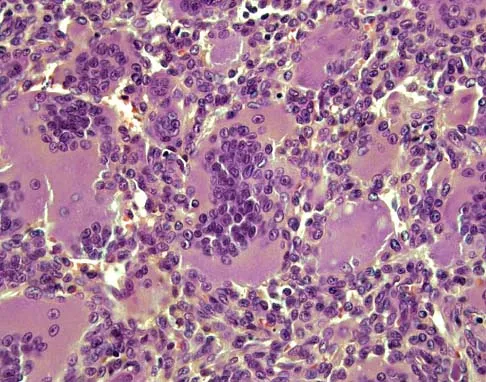

A 19-year-old girl has had pain and swelling in the right ankle for the past 4 months. She denies any history of trauma. Examination reveals a small soft-tissue mass over the anterior aspect of the ankle and slight pain with range of motion of the ankle joint. The examination is otherwise unremarkable. A radiograph and MRI scan are shown in Figures 45a and 45b, and biopsy specimens are shown in Figures 45c and 45d. What is the most likely diagnosis?

Explanation